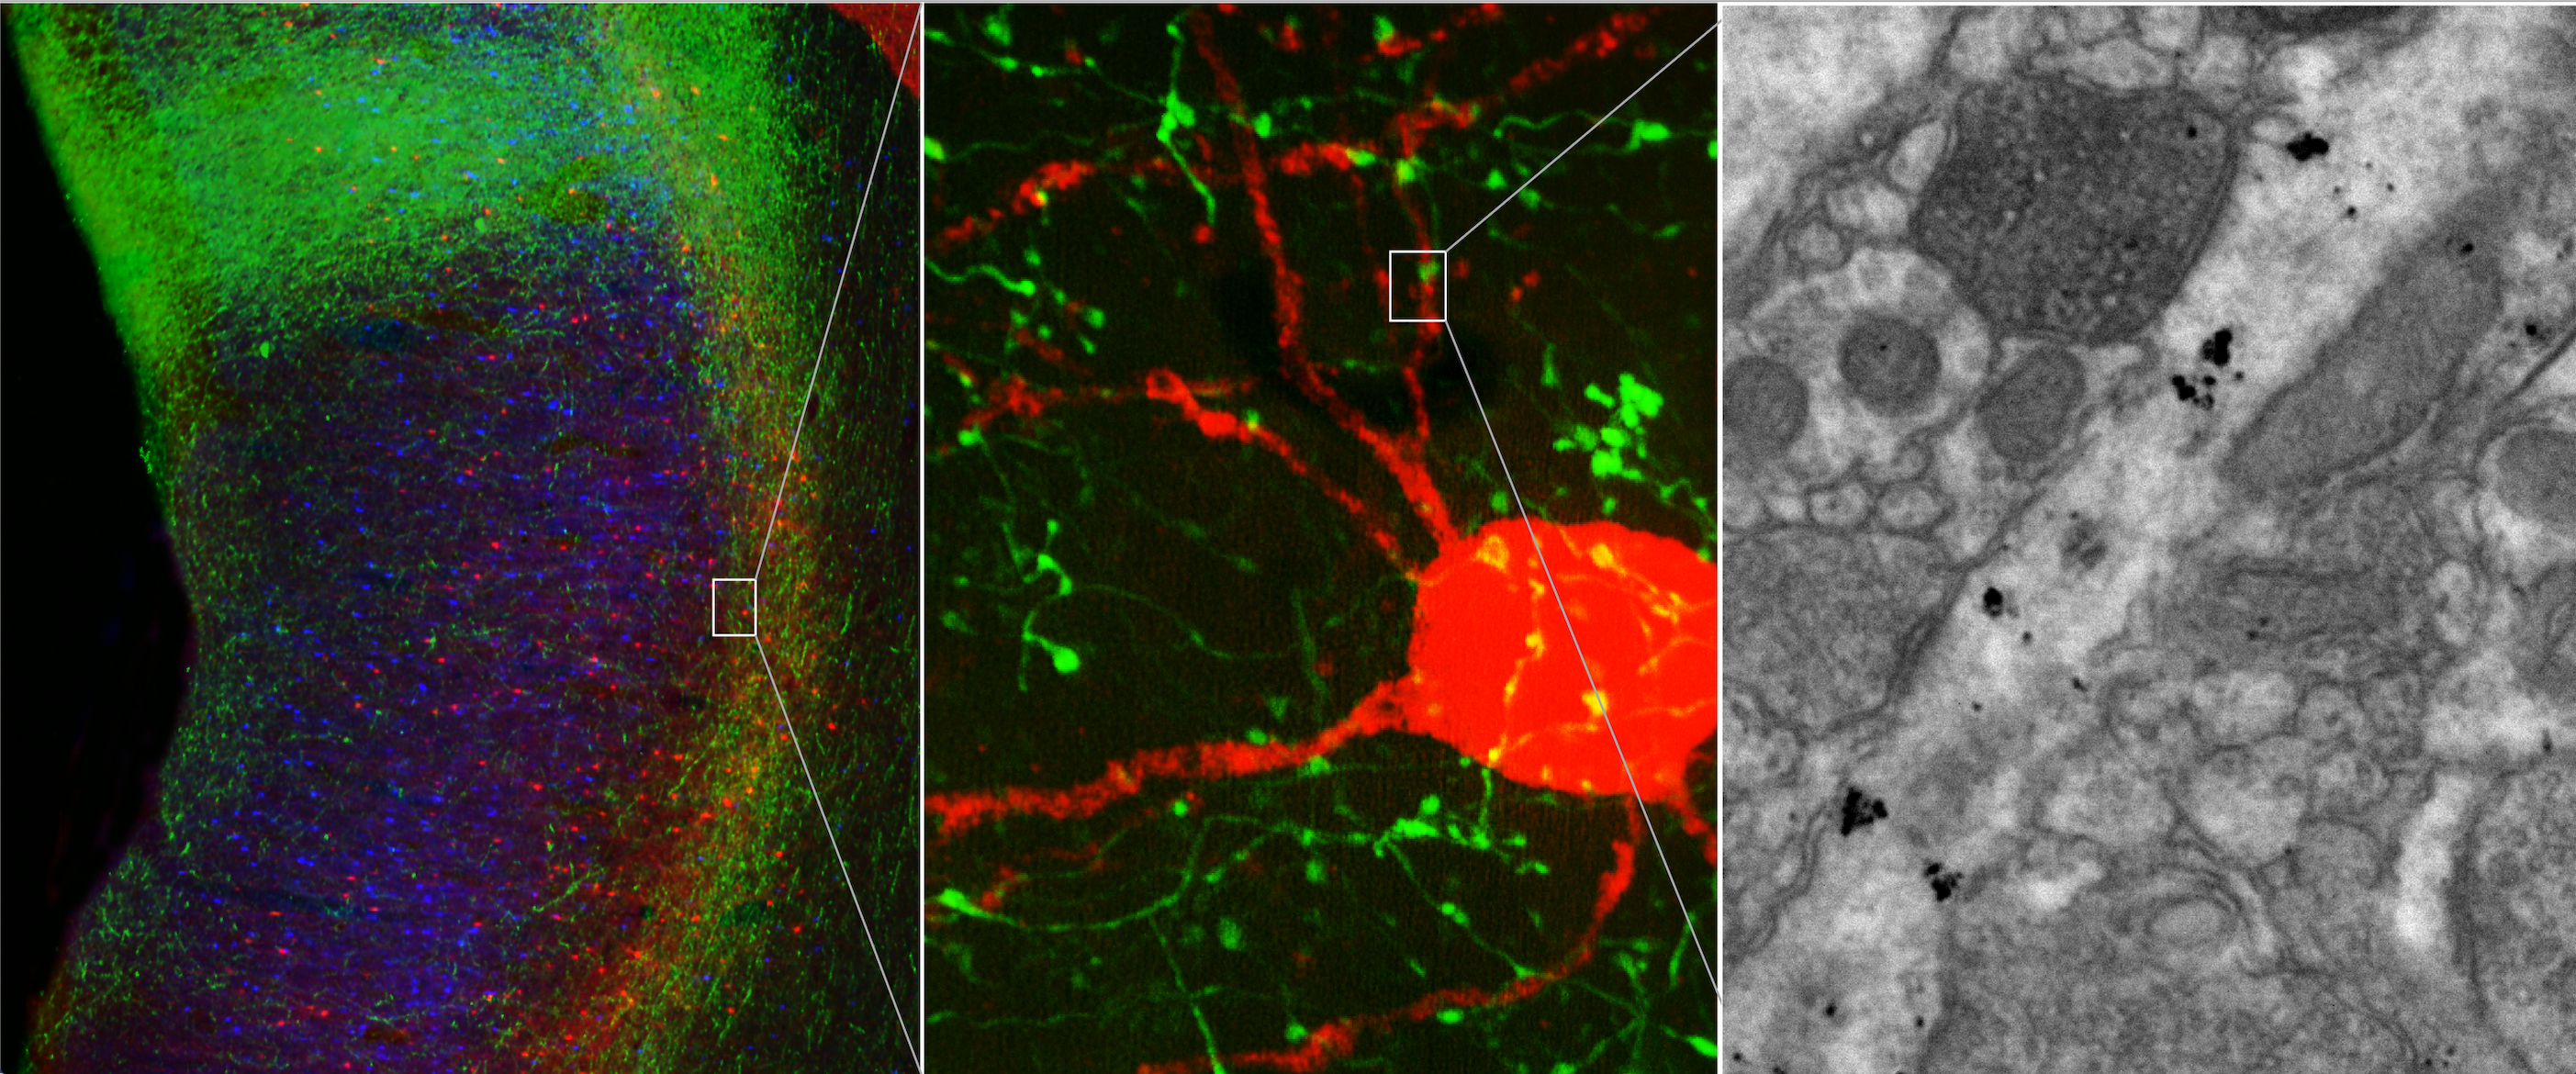

The researchers identified area 32 using neural tracers to visualize the connections between cognitive (DLPFC) and emotional (area 25) brain regions in rhesus monkeys. Their discovery helps us better understand what makes certain people more susceptible to depression — and can inform different treatment approaches.

So, what do these critical interactions between brain regions actually look like? The researchers take us into their lab for an inside-look: